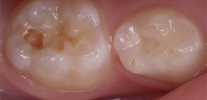

Dopo il trattamento con una soluzione colorante della cavità cariata, è sufficiente che il medico pulisca i tessuti colorati con l'indicatore con un trapano e, dopo ogni rimozione, tratti le pareti della cavità con una nuova porzione del marker. Questa procedura si ripete fino a quando le pareti della cavità non smettono affatto di macchiarsi, il che indicherà la completa rimozione dei tessuti colpiti dalla carie.

Durante il trattamento con un trapano, tutti i tessuti tinti nel colore dell'indicatore vengono rimossi con il boro. Successivamente, le pareti della cavità vengono nuovamente trattate con un pennarello per 5-10 secondi e nuovamente sciacquate con acqua. Quando vengono visualizzate nuove aree colorate, vengono nuovamente rimosse. La procedura viene ripetuta fino a quando la colorazione con il marker si interrompe durante l'elaborazione di tutte le pareti della cavità.